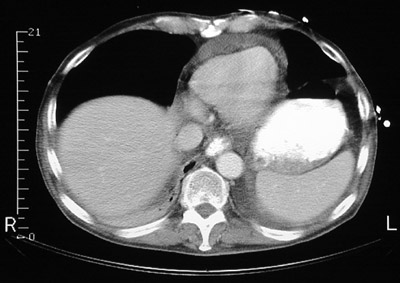

| This CT scan at the level of the lower chest demonstrates a large pericardial effusion around the heart. The dome of the liver appears at the right. There is also ascitic fluid around the spleen. This patient had severe congestive heart failure. Contrast fills the stomach. |